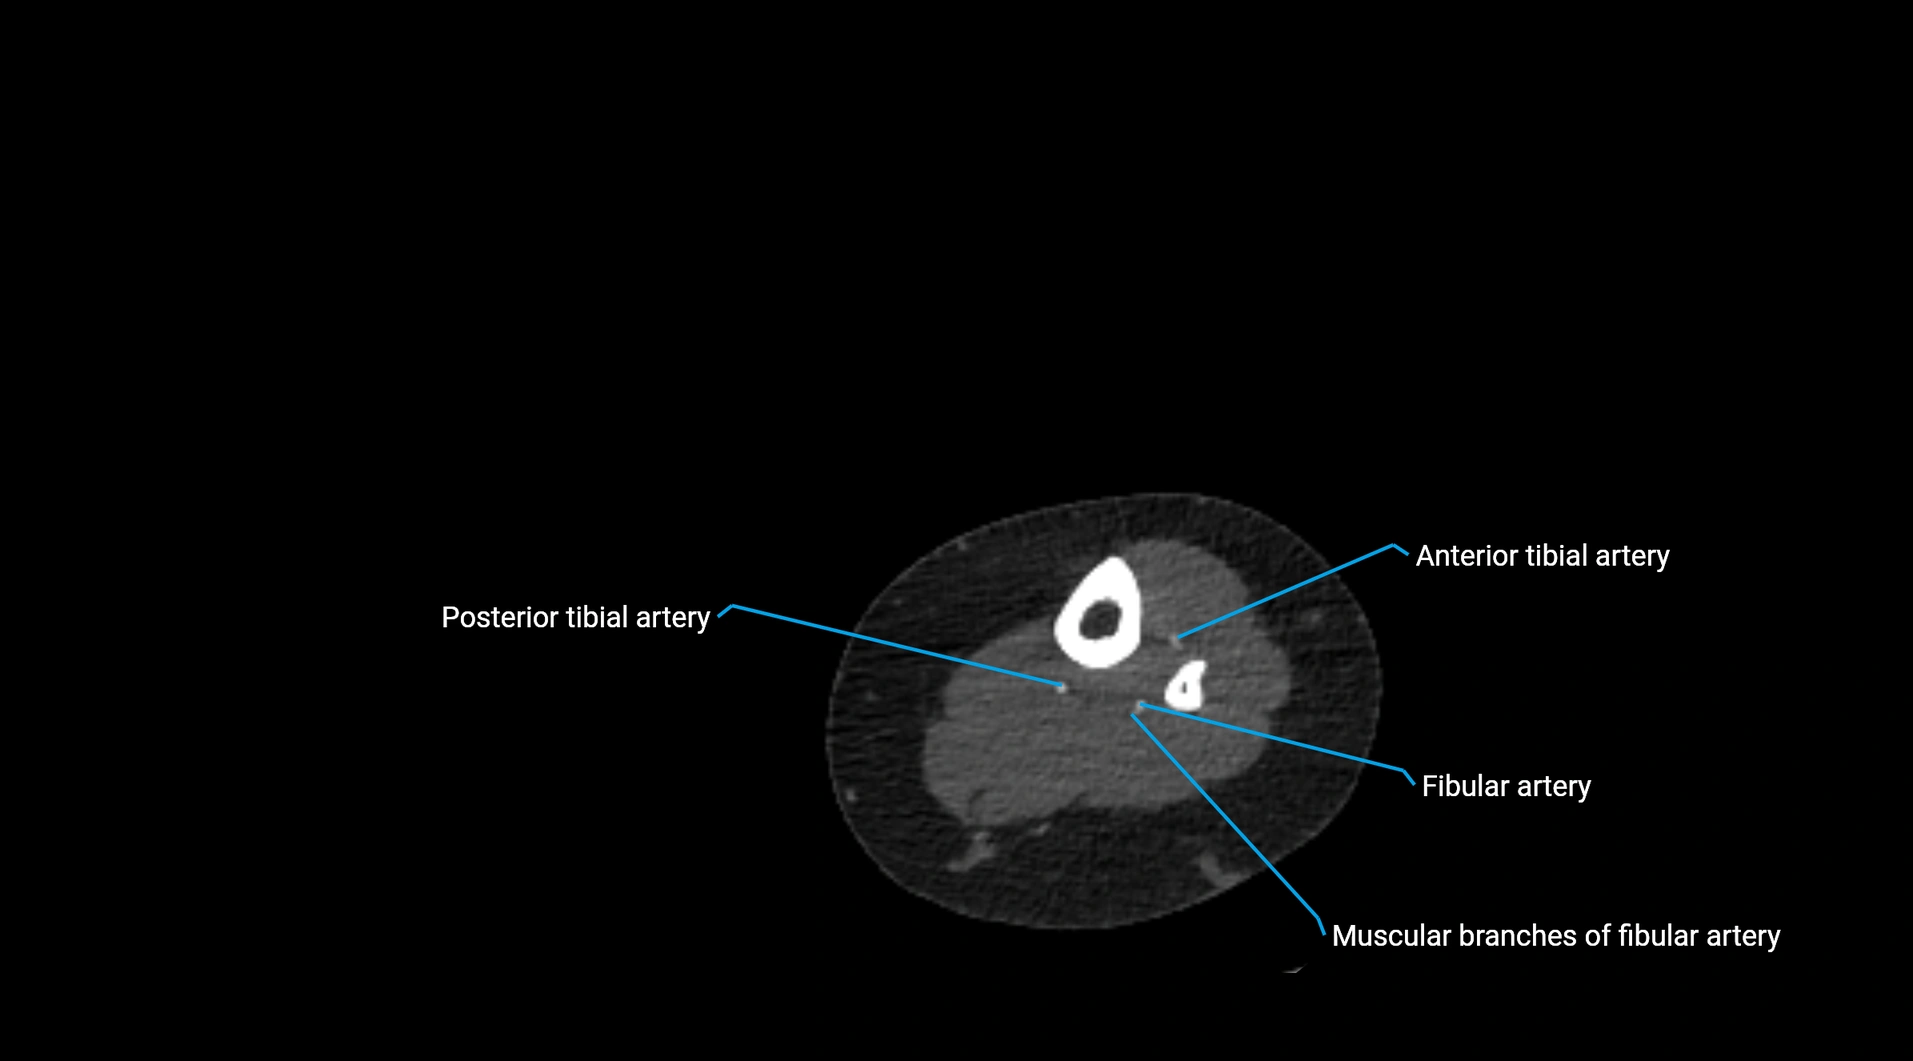

CT Appearance

Non-contrast CT:

• Appears as a tubular soft tissue structure anterior to vertebral bodies

• Calcified atherosclerotic plaques appear as hyperdense foci along the wall

• Useful for screening abdominal aortic aneurysm (AAA) size and mural calcification

Contrast-enhanced CT (CTA):

• Gold standard for abdominal aortic imaging

• Provides excellent detail of lumen, wall, aneurysm, thrombus, and branch vessels

• Multiplanar and 3D reconstructions help in aneurysm measurement, stent graft planning, and dissection evaluation

• Detects acute rupture, traumatic injury, or occlusion with high sensitivity